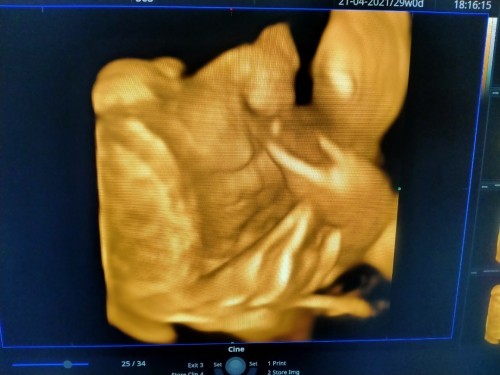

เเม่ๆช่วยดูภาพอัลตร้าซาวด์ทีค่ะ ปากน้องปกติทั่วไปใช่ไหม?(เเม่คิดมากแอบเห็นรอยหยักตรงปากบน) เเม่กลัวลูกเกิดมาผิดปกติค่ะ

รูปนี้ซาวตอนกี่วีคคะ ... ถ้าจะเห็นชัดๆ ต้องช่วง 8 เดือน ถ้าอายุครรภ์ยังน้อย ภาพที่ได้น้องอาจจะยังโตไม่เต็มที่ เพียงแค่ให้เห็นว่าโครงสร้างเริ่มมีเป็นรูปเป็นร่างแล้ว เราแนะนำนะคะ ถ้าสงสัยหรือกังวล ให้ถามหมอตอนนั้นเลย ... เราดูจากตรงนี้ไม่สามารถตอบได้ว่าน้องผิดปกติมั้ย หมอชัวร์สุดคะ #ระหว่างตรวจหมอจะอธิบายและตรวจตามอวัยวะต่างๆว่าน้องมีอาการปกติหรือไม่นะคะ

จริงๆรูปนี้มันดูยากมากเลยนะคะ ตรงไหนตา จมูก ปาก ดูไม่ค่อยออกเลยค่ะเเม่มันอาจจะเป็นรอยน้ำคล่ำรึเปล่าถ้าปากเเหว่งหมอต้องบอกเเม่อยู่เเล้วค่ะ รอบหน้าเเม่ลองเอารูปนี้ไห้หมอดูเเล้วลองถามหมออีกทีดูค่ะ

ถ้าผิดปกติหมอต้องบอกแล้วนะคะแม่ แม่มีรูปที่ชัดกว่านี้ไหมคะ บางทีอาจจะเป็นเพราะน้องขยับตัวหรือสายสะดือบังอ่ะค่ะ อันนี้ของเราเพิ่งซาวด์28wค่ะ จะชัดแบบนี้

เห็นหยักนิดหน่อย แต่ขอหมอดู และให้หมอแจ้งอีกทีนะคะ บางทีอาจเป็นมุมภาพก็ได้ บ้านนี้หมอซูมตรงริมฝีปากให้เลยค่ะ แจ้งละเอียดมาก ฝากบัตร 30 บาท 😊

รูปไม่ชัดเลยคะ ถ้าซาวด์ 4 มิติ ผิดปกติหมอจะแจ้งนะคะ เพราะยังไงก็เห็นละเอียดกว่า 2 มิติ